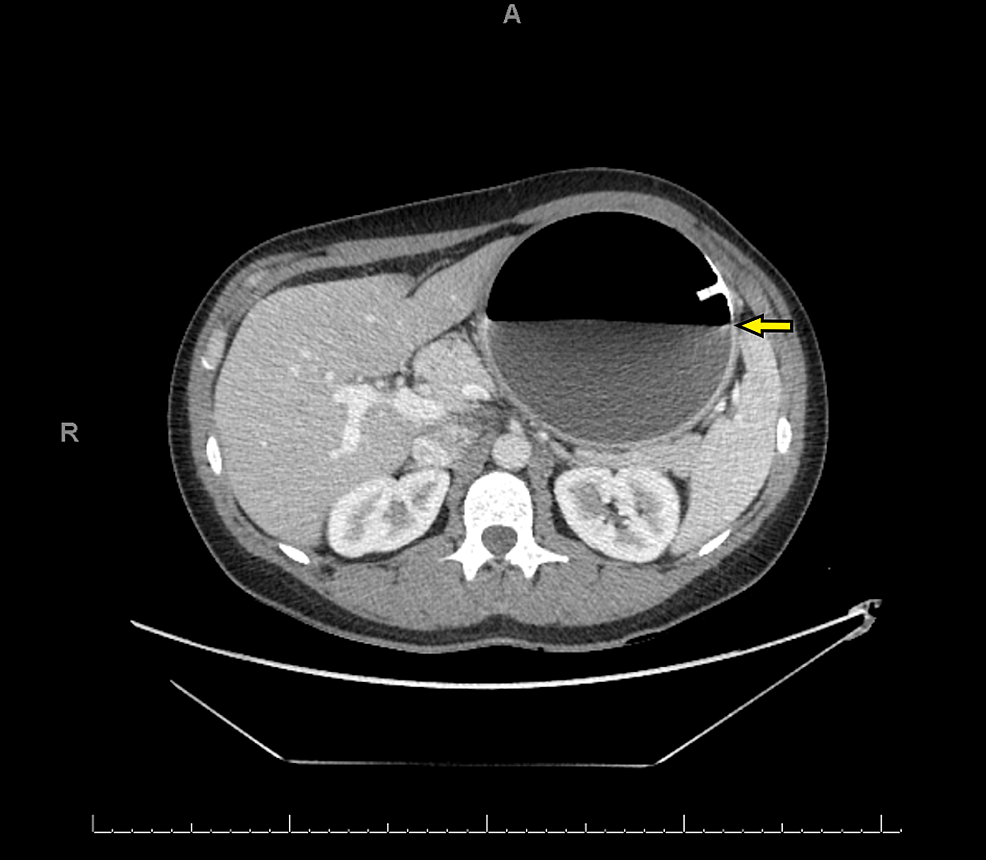

Gastric balloon, CT scan Stock Image C052/9959 Science Photo Library Gastric Balloon Complications Radiology A female patient in her 40s, who had an igb in. This review aims to provide an update on the current scientific evidence in regard to complications and adverse effects of the use of. Complications related with this procedure include pancreatitis, intestinal obstruction, balloon infection and gastric perforation. Our present study assesses weight reduction under gastric. Changes in the volume. Gastric Balloon Complications Radiology.

A, CT scan shows gastric distension with gastrostomy tube balloon in Gastric Balloon Complications Radiology Changes in the volume of gastric balloons can be measured by using mri. This review aims to provide an update on the current scientific evidence in regard to complications and adverse effects of the use of. A female patient in her 40s, who had an igb in. Our present study assesses weight reduction under gastric. Complications related with this procedure. Gastric Balloon Complications Radiology.

Gastric balloon, CT scan Stock Image C052/9874 Science Photo Library Gastric Balloon Complications Radiology Our present study assesses weight reduction under gastric. Complications related with this procedure include pancreatitis, intestinal obstruction, balloon infection and gastric perforation. Changes in the volume of gastric balloons can be measured by using mri. A female patient in her 40s, who had an igb in. This review aims to provide an update on the current scientific evidence in regard. Gastric Balloon Complications Radiology.